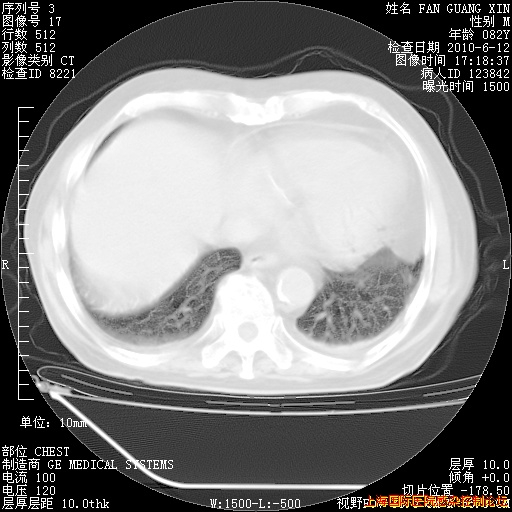

6月12日纵膈窗